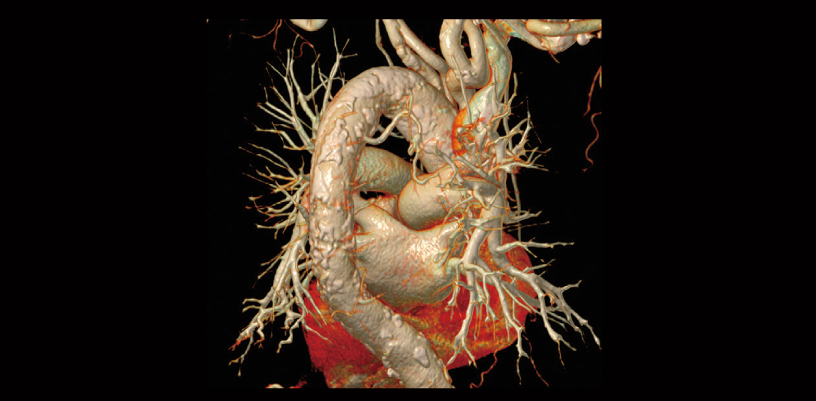

Seguimiento después de CABG